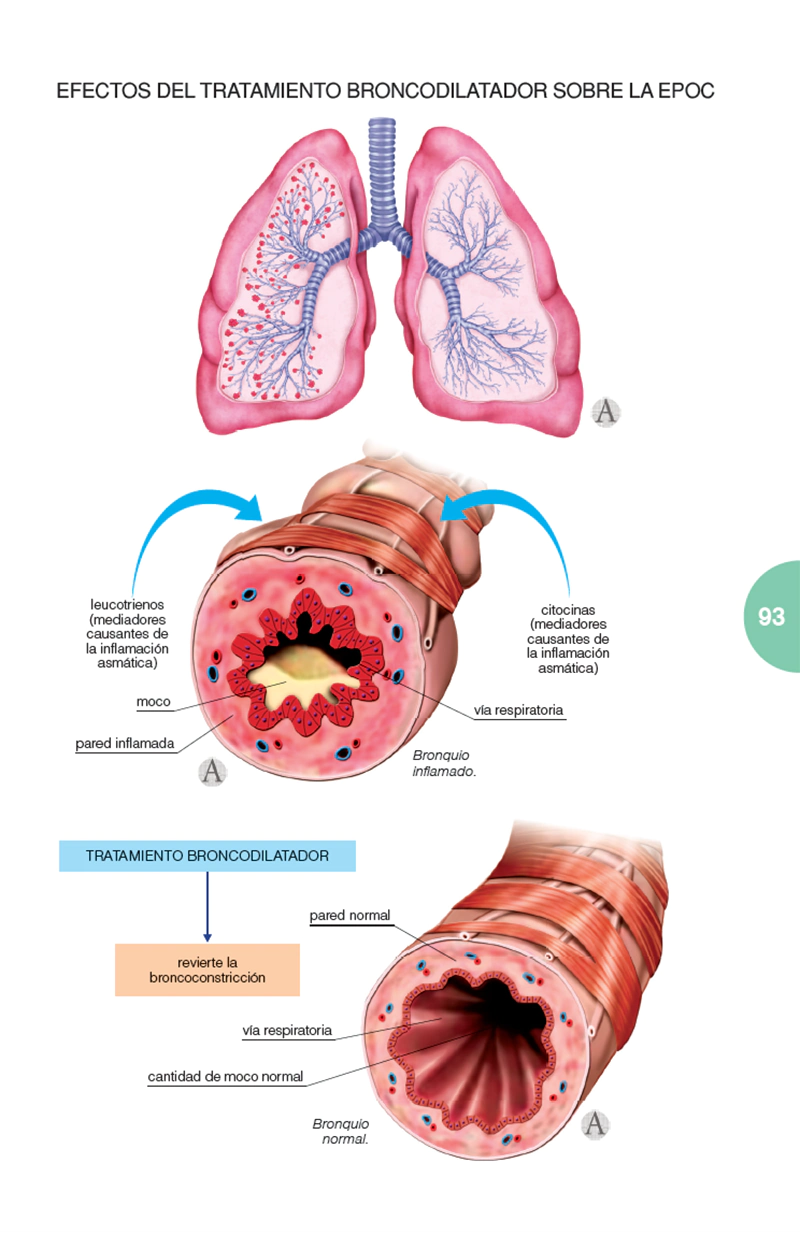

Un libro de la extensión de este no puede explicarlo todo sobre el tema. Pero sí aporta una cantidad más que suficiente de información para que tanto el profesional, como el paciente puedan encontrar en él todo aquello que constituye el núcleo fundamental de conocimientos sobre la enfermedad, además de un gran acopio de materiales complementarios, tanto de tipo ilustrativo como, sobre todo, práctico, que servirán eficientemente para conocer en su globalidad qué es la EPOC, cómo tratarla y la manera más adecuada para que el paciente pueda hacerle frente.